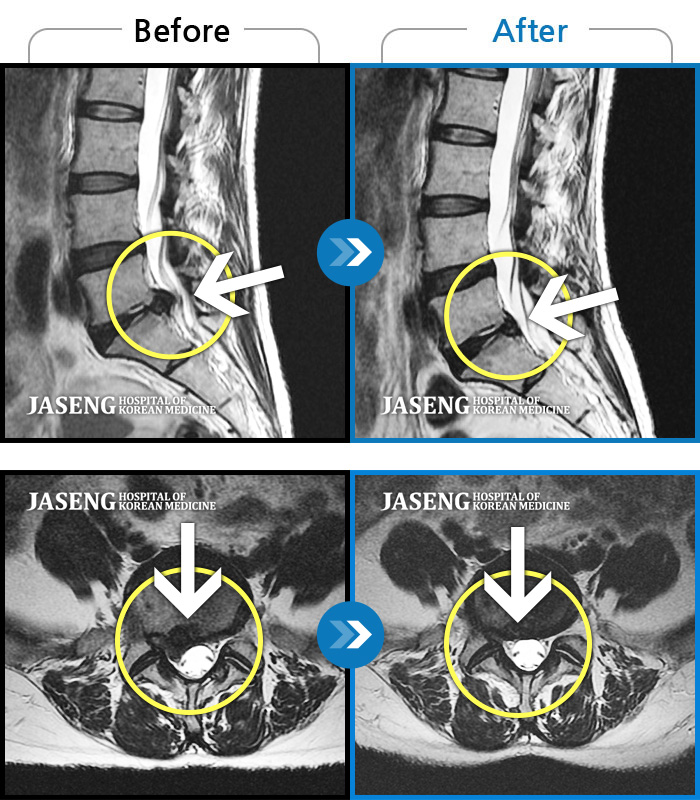

[뱸] 19.11.28~25.05.06

ȯںп Ǹ ǿ ԿǾ, ο ġ ۿ Ƿ ġḦ Ͻñ ٶϴ.